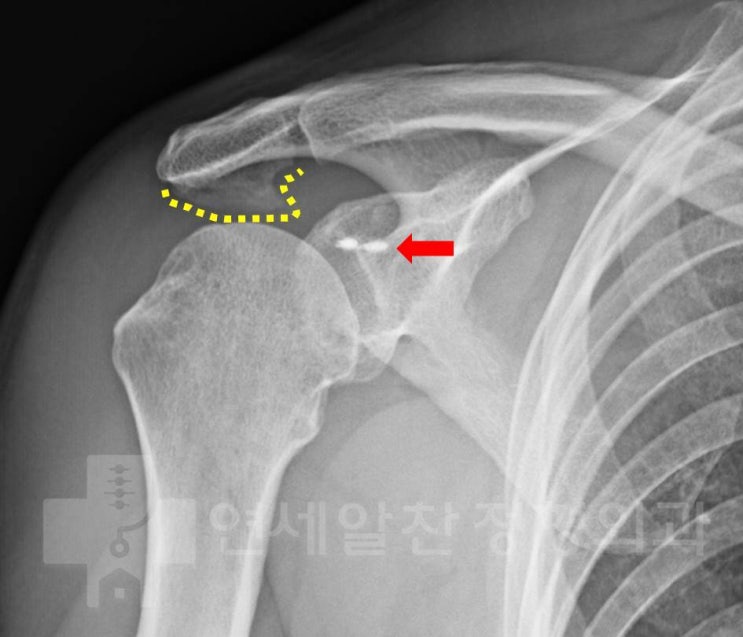

거대한 석회성 건염에서 관절경을 통한 석회 제거술 및 극상근 봉합술(side to side)

43에 여자 환자로 우측 어깨의 극심한 통증을 주소로 내원하였다. 환자는 내원 일주일 전부터 극심한 통증...